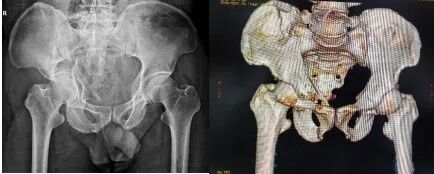

术后DR与CT显示骨折复位固定好,关节面平整

手术期间,骨科团队按照术前规划,精准入路完成了良好的复位和固定,整个手术用时短,创伤小,出血量显著减少,患者疼痛轻。术后复查显示,关节面平整,头臼关系匹配良好,且患者恢复迅速。